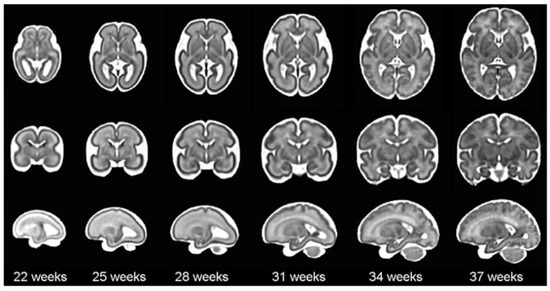

Figure 2 illustrates an example of a premature baby acquisition for both the coronal and sagittal planes. The images of each infant were acquired over several weeks, ranging from 24 to 30 weeks. The images were obtained following anatomical references for different planes:

• Coronal plane: orbital border ( c 1 ), sphenoidal ridge ( c 2 ), foramina of Monro and third ventricle ( c 3 ), fourth ventricle ( c 4 ), choroid plexus ( c 5 ), and visibility of the parietooccipital sulcus in the inferior tier of the image ( c 6 ).

• Sagittal plane: midsagittal ( s 1 ), lateral ventricles ( s 2 l , s 2 r ), lateral fissure ( s 3 r ), and lateral fissure at the bottom of the image ( s 4 l , s 4 r ).

Figure 2. Plans used in the study of a premature baby. For the coronal plane and following the alphabetical order from (a) to (f), we have the planes of c 1 , c 2 , c 3 , c 4 , c 5 , and c 6 ; and following the same order but starting with (g) and ending with (m), the sagittal planes s 1 , s 2 l , s 2 r , s 3 l , s 3 r , s 4 l , and s 4 r .